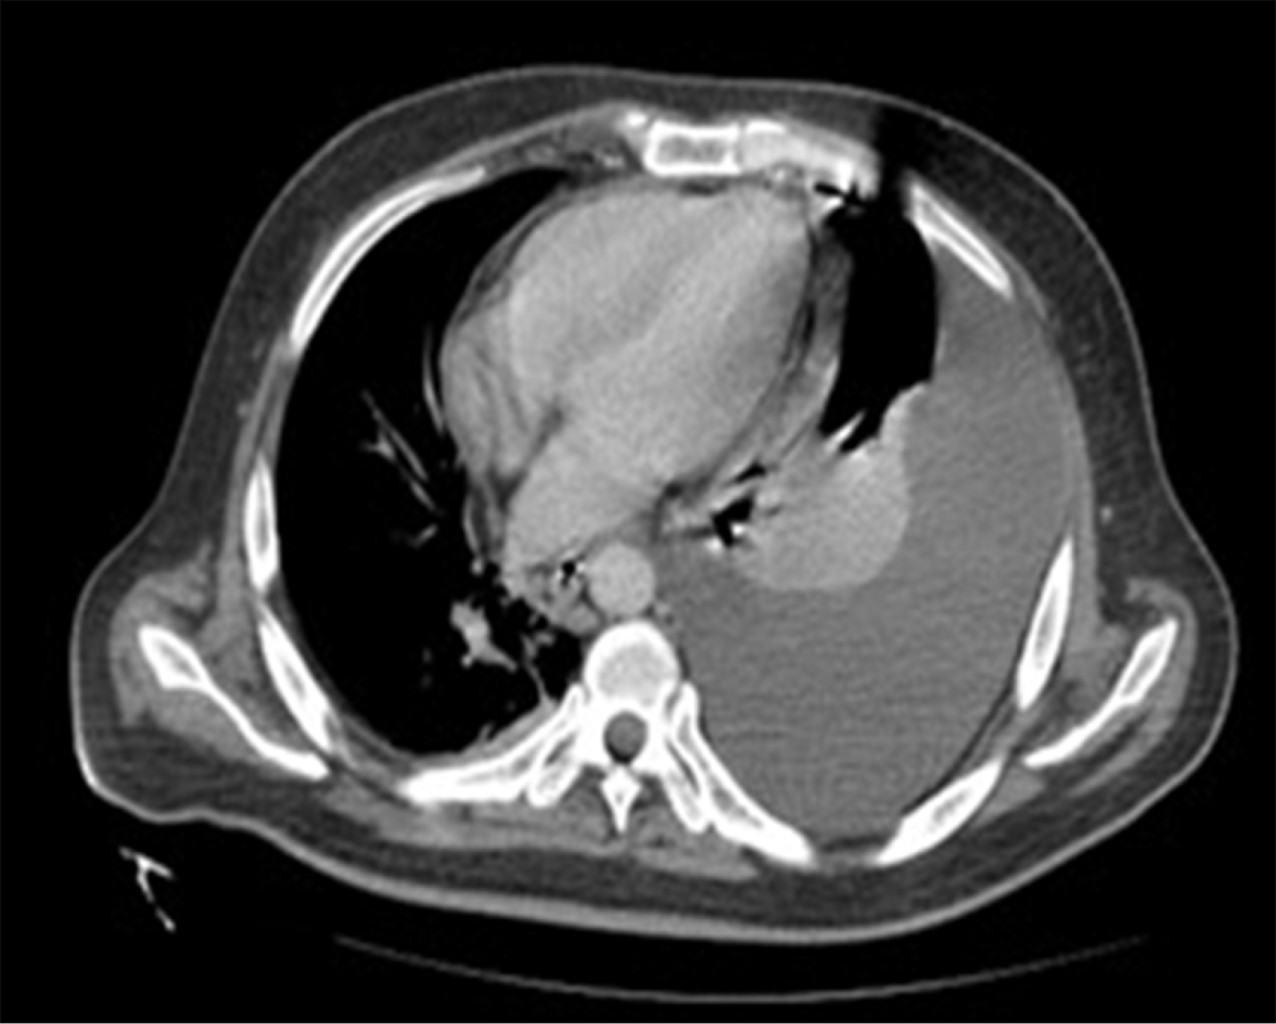

An anteroposterior (AP) chest X-ray was performed, in which a left pleural effusion covering more than 50% was visualized. A computed tomography scan showed a significant amount of fluid in the left pleural space that conditioned a passive atelectasis of the lower lobe (Figure 1); the liver was found with heterogeneous density with an increase of the left hepatic lobe secondary to the presence of a heterogeneous hypodense lesion with lobulated borders, showing peripheral reinforcement and some internal septa covering segments II, III, IVa, and IVb measuring approximately 20 × 14.5 × 12.5 cm (Figure 2), conditioning posterior displacement and compression of the stomach and pancreas and caudal displacement of the intestinal loops (Figures 3 and 4). In the lower pole of the right hepatic lobe adjacent to segment IV, a homogeneous cystic lesion with peripheral enhancement was identified after intravenous contrast administration, measuring 25 × 27 × 13 cm in its major axes. A Foley tube and nasogastric tube were placed as initial management draining a liquid of gastric characteristics (30 ml). A central catheter was placed and verified by radiography. Imaging studies were requested. Fasting was ordered and fluid therapy, antibiotic therapy with ceftriaxone and metronidazole, pain management, glycemic control, and gastric protection were started. When visualizing the image of the left pleural effusion, it was decided to perform a thoracentesis, obtaining a thick exudate with a chocolate appearance. When the tomography was available, urgent surgical treatment was performed.

Figure 2